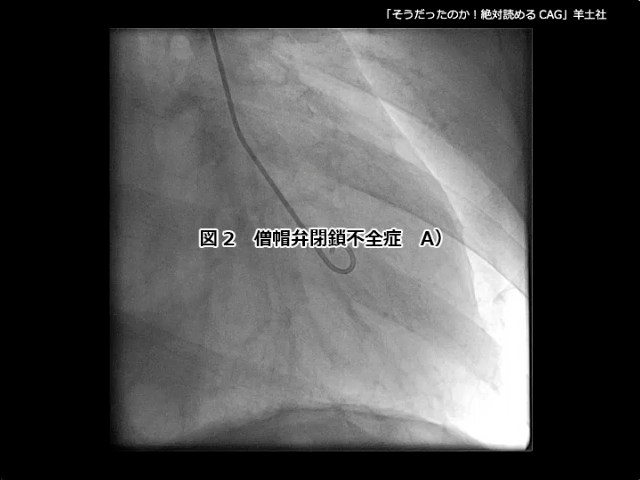

第5章-1 急性冠症候群の造影所見